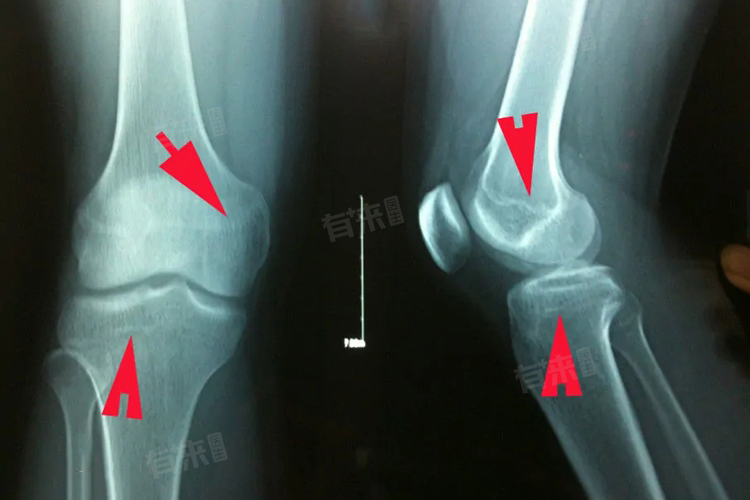

1、X光检查:这是最常用且较为准确的判断方法,通过拍摄特定部位的X光片,如手腕、膝关节等部位,可以清晰地看到骨骺线的状态,在X光片上,如果骨骺线表现为一条清晰的线状影,说明骨骼线尚未闭合,骨骼仍有生长的潜力。随着年龄的增长,当骨骺线逐渐变窄、模糊,最终与骨干融合,形成一条致密的线时,则表示骨骼线已经闭合,骨骼停止生长。